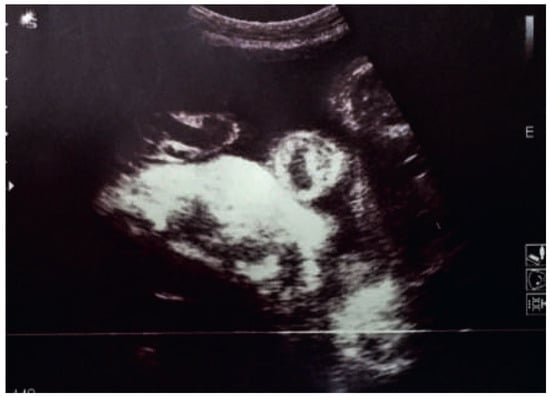

Ectopia Cordis